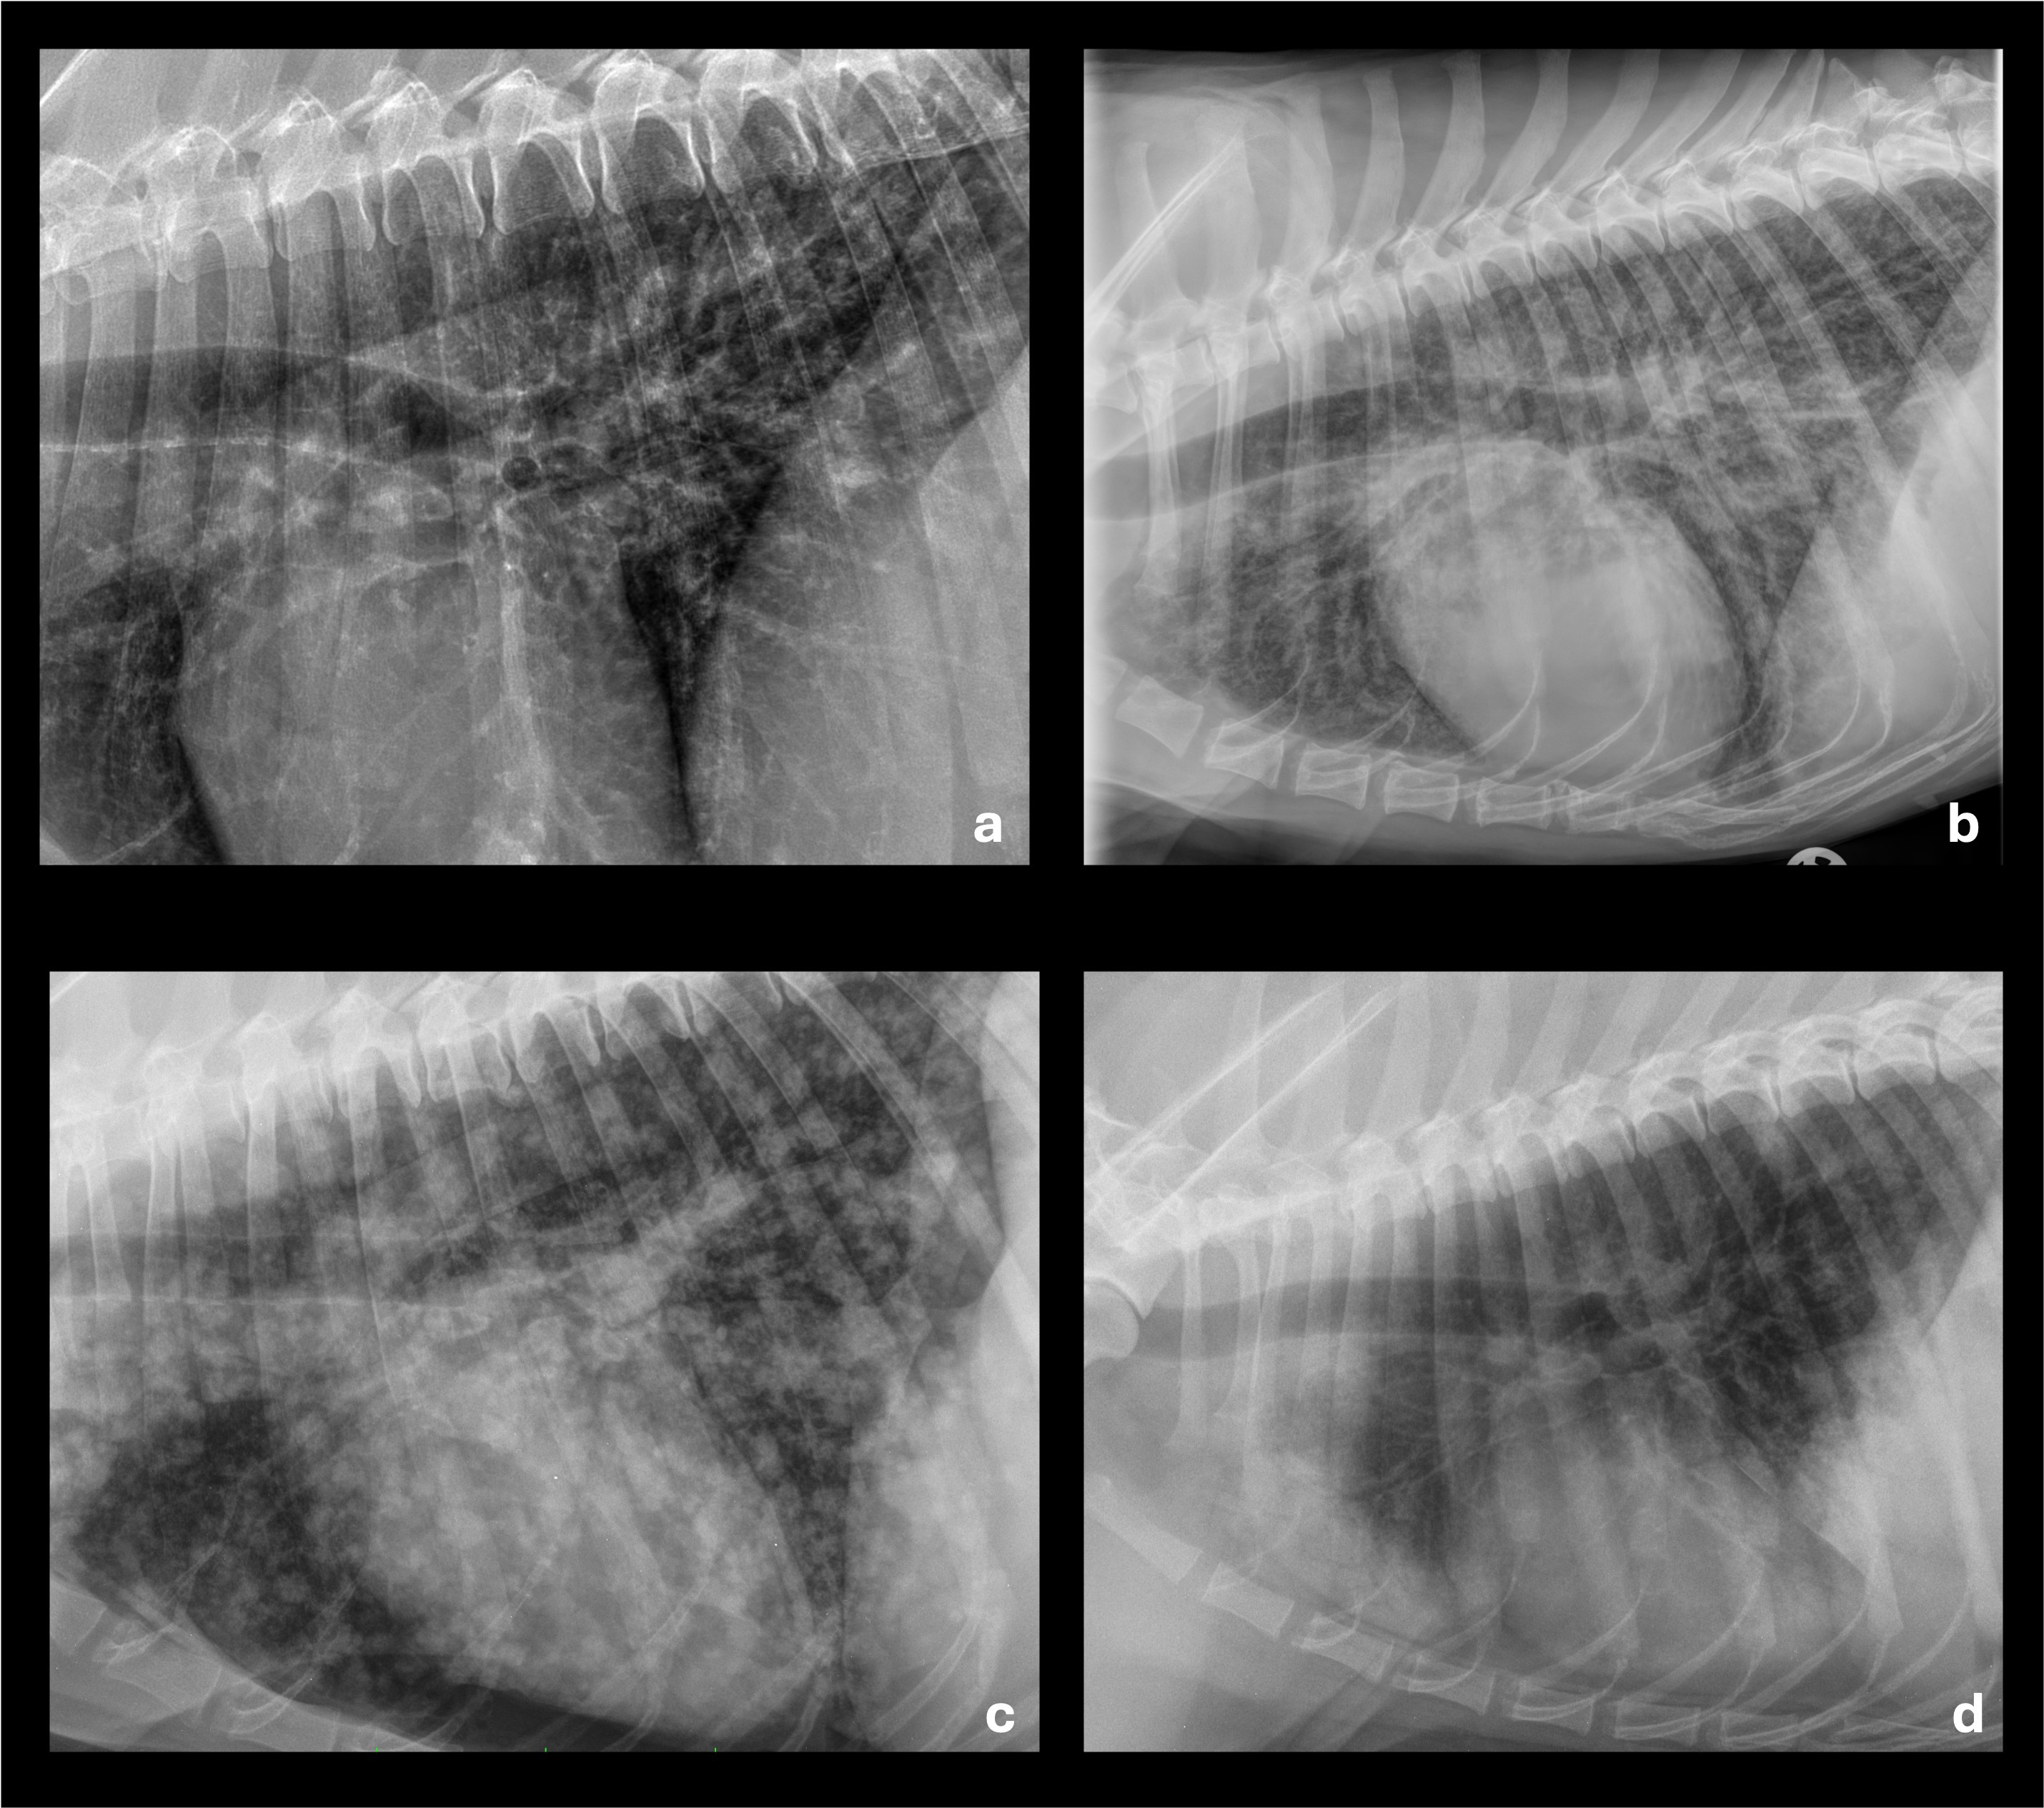

Ein wesentlicher Vorteil der CT liegt in der morphologischen Subklassifikation von Veränderungen, die im Röntgen lediglich als „interstitiell“ imponieren. Ground-glass-Opazitäten, Konsolidierungen, retikuläre Veränderungen oder endobronchiale Muster (z. B. „tree-in-bud“) lassen sich differenzieren und klinisch einordnen (Abb. 2). Dies ist entscheidend für die Abgrenzung zwischen entzündlichen, ödematösen, hämorrhagischen oder atelektatischen Prozessen.

Ein wichtiger Interpretationsaspekt ist die lagerungs- und narkosebedingte Atelektase, die vor allem in abhängigen Lungenarealen auftritt und entzündliche Veränderungen vortäuschen kann. Standardisierte CT-Protokolle, kurze Atemstillstände und eine bewusste Bewertung der Verteilungsmuster sind essenziell, um Fehldiagnosen zu vermeiden. In Tabelle 2 finden sich verschiedene CT-Befunde mit den markanten morphologischen Merkmalen und der klinischen Interpretation.